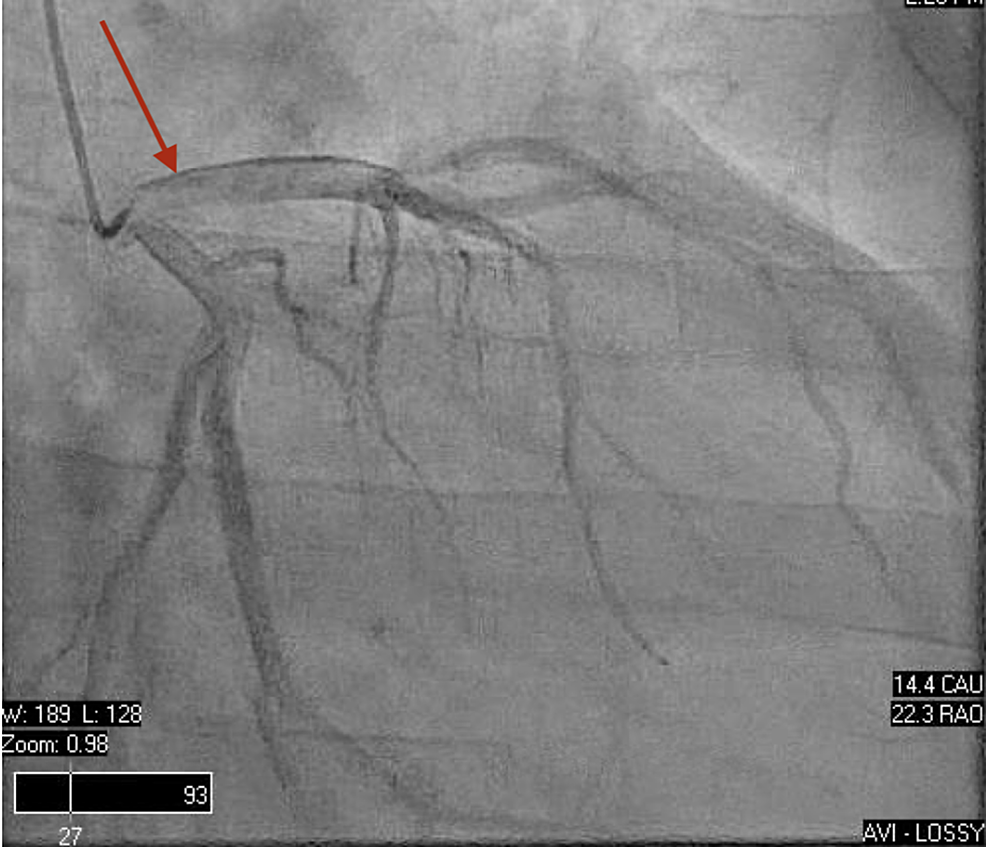

Figure 2. Cardiac catheterization which revealed anterolateral and Cardiac Catheterization Ejection Fraction When the heart squeezes, it's. Ejection fraction is a measurement doctors can use to help diagnose heart failure. A normal heart’s ejection fraction is between 55 and 70 percent. A normal range is between 52% and 72% for males and between. A normal ejection fraction is 50 percent or. A normal ejection fraction is about 55% to 70%. Ejection fraction. Cardiac Catheterization Ejection Fraction.